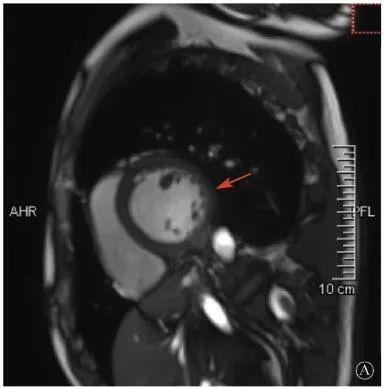

患者入院后無(wú)特殊不適,心率70次/min,血壓110/60 mmHg,心功能Ⅱ級(jí)。查血常規(guī):血紅蛋白139 g/L,白細(xì)胞7.39×109/L,血小板221×109/L。尿常規(guī)、便常規(guī)+潛血均正常。生化:丙氨酸氨基轉(zhuǎn)移酶38 U/L,白蛋白47 g/L,鉀3.9 mmol/L,肌酐(酶法)65 μmol/L,總膽固醇3.52 mmol/L,低密度脂蛋白膽固醇2.08 mmol/L。CK:1256→487 U/L,CK-MB 9.7→3.8 μg/L,cTnI 85.90→68.50 pg/ml。N末端B型利鈉肽原70 pg/ml。CK同工酶電泳:肌酸激酶MM質(zhì)量100.0%(此時(shí)CK-MB已正常)。血沉1 mm/第1小時(shí),高敏C反應(yīng)蛋白1.61 mg/L;補(bǔ)體:C3 0.876 g/L,C4 0.174 g/L。免疫球蛋白:IgG 9.52 g/L,IgA 1.73 g/L,IgM 0.62 g/L。血清蛋白電泳未見(jiàn)M蛋白。糖化血紅蛋白5.1%。乳酸(運(yùn)動(dòng)前)1.1 mmol/L,乳酸(運(yùn)動(dòng)中)6.6 mmol/L,乳酸(運(yùn)動(dòng)后)7.8 mmol/L。肌炎抗體譜:抗PM-SCL75(+),余均(-)。心電圖:aVL、V5、V6導(dǎo)聯(lián)T波倒置(圖2)。冠狀動(dòng)脈CT未見(jiàn)明顯異常。超聲心動(dòng)圖:左室舒張末內(nèi)徑55 mm,左室收縮功能減低,心尖部、左室壁普遍運(yùn)動(dòng)減低,以左室下后壁為著,左室下后壁肌小梁明顯增多可見(jiàn)隱窩,疏松層與致密層之比為1.7;左室射血分?jǐn)?shù)(雙平面)45%;右冠狀動(dòng)脈開(kāi)口6.5 mm,開(kāi)口處未見(jiàn)明確瘤樣擴(kuò)張(圖3)。

B:胸骨旁左室短軸切面心尖水平,可見(jiàn)心肌肌小梁增多,其內(nèi)可見(jiàn)隱窩(箭頭所示)

圖3 患者入院后超聲心動(dòng)圖